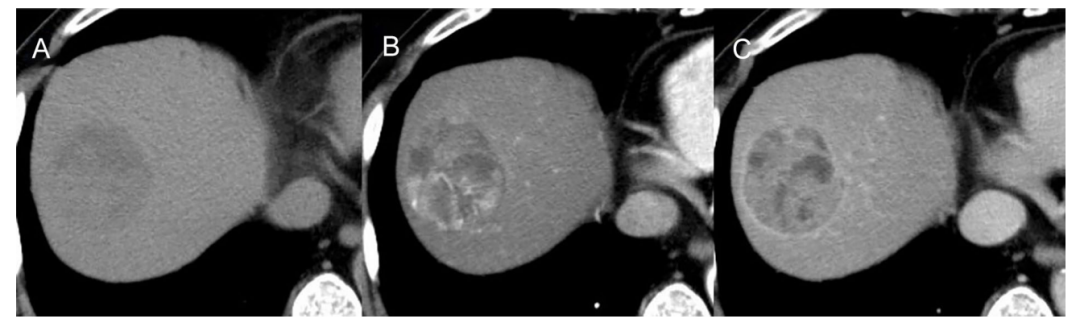

腹部动态CT显示一个直径54mm的圆形低密度S8肿瘤,在动脉期增强,在门静脉期和延迟期清除。基于患者的酒精性肝病史而被诊断为HCC。

因此,在首次治疗后5个月开始接受阿替利珠单抗+贝伐珠单抗联合治疗。在给予联合治疗两个疗程后,CT扫描显示肺部肿瘤、左髂肿瘤和盆腔淋巴结肿瘤生长。肺部也有新的病变,提示疾病进展(PD)。肿瘤标志物水平也有所升高。

虽然考虑改变治疗方案,但在医生酌情思考后,决定继续进行联合治疗。在给予阿替利珠单抗加贝伐珠单抗三个疗程后,CT扫描显示肺和髂肿瘤均减少。在第四个疗程结束后,CT扫描显示肺部肿瘤消失。在给予联合治疗5个疗程后,CT扫描显示肺肿瘤无复发,髂和盆腔淋巴结转移进一步减少,疗效评估达到部分缓解(PR)。随着肿瘤的减小,肿瘤标志物水平也降低。